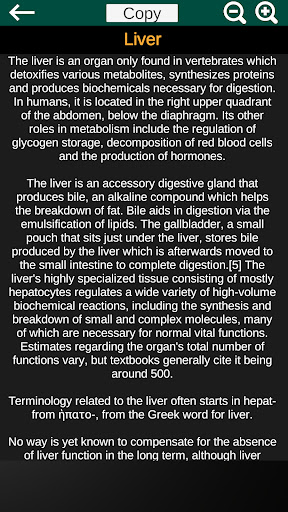

* Descriptions of each organ.